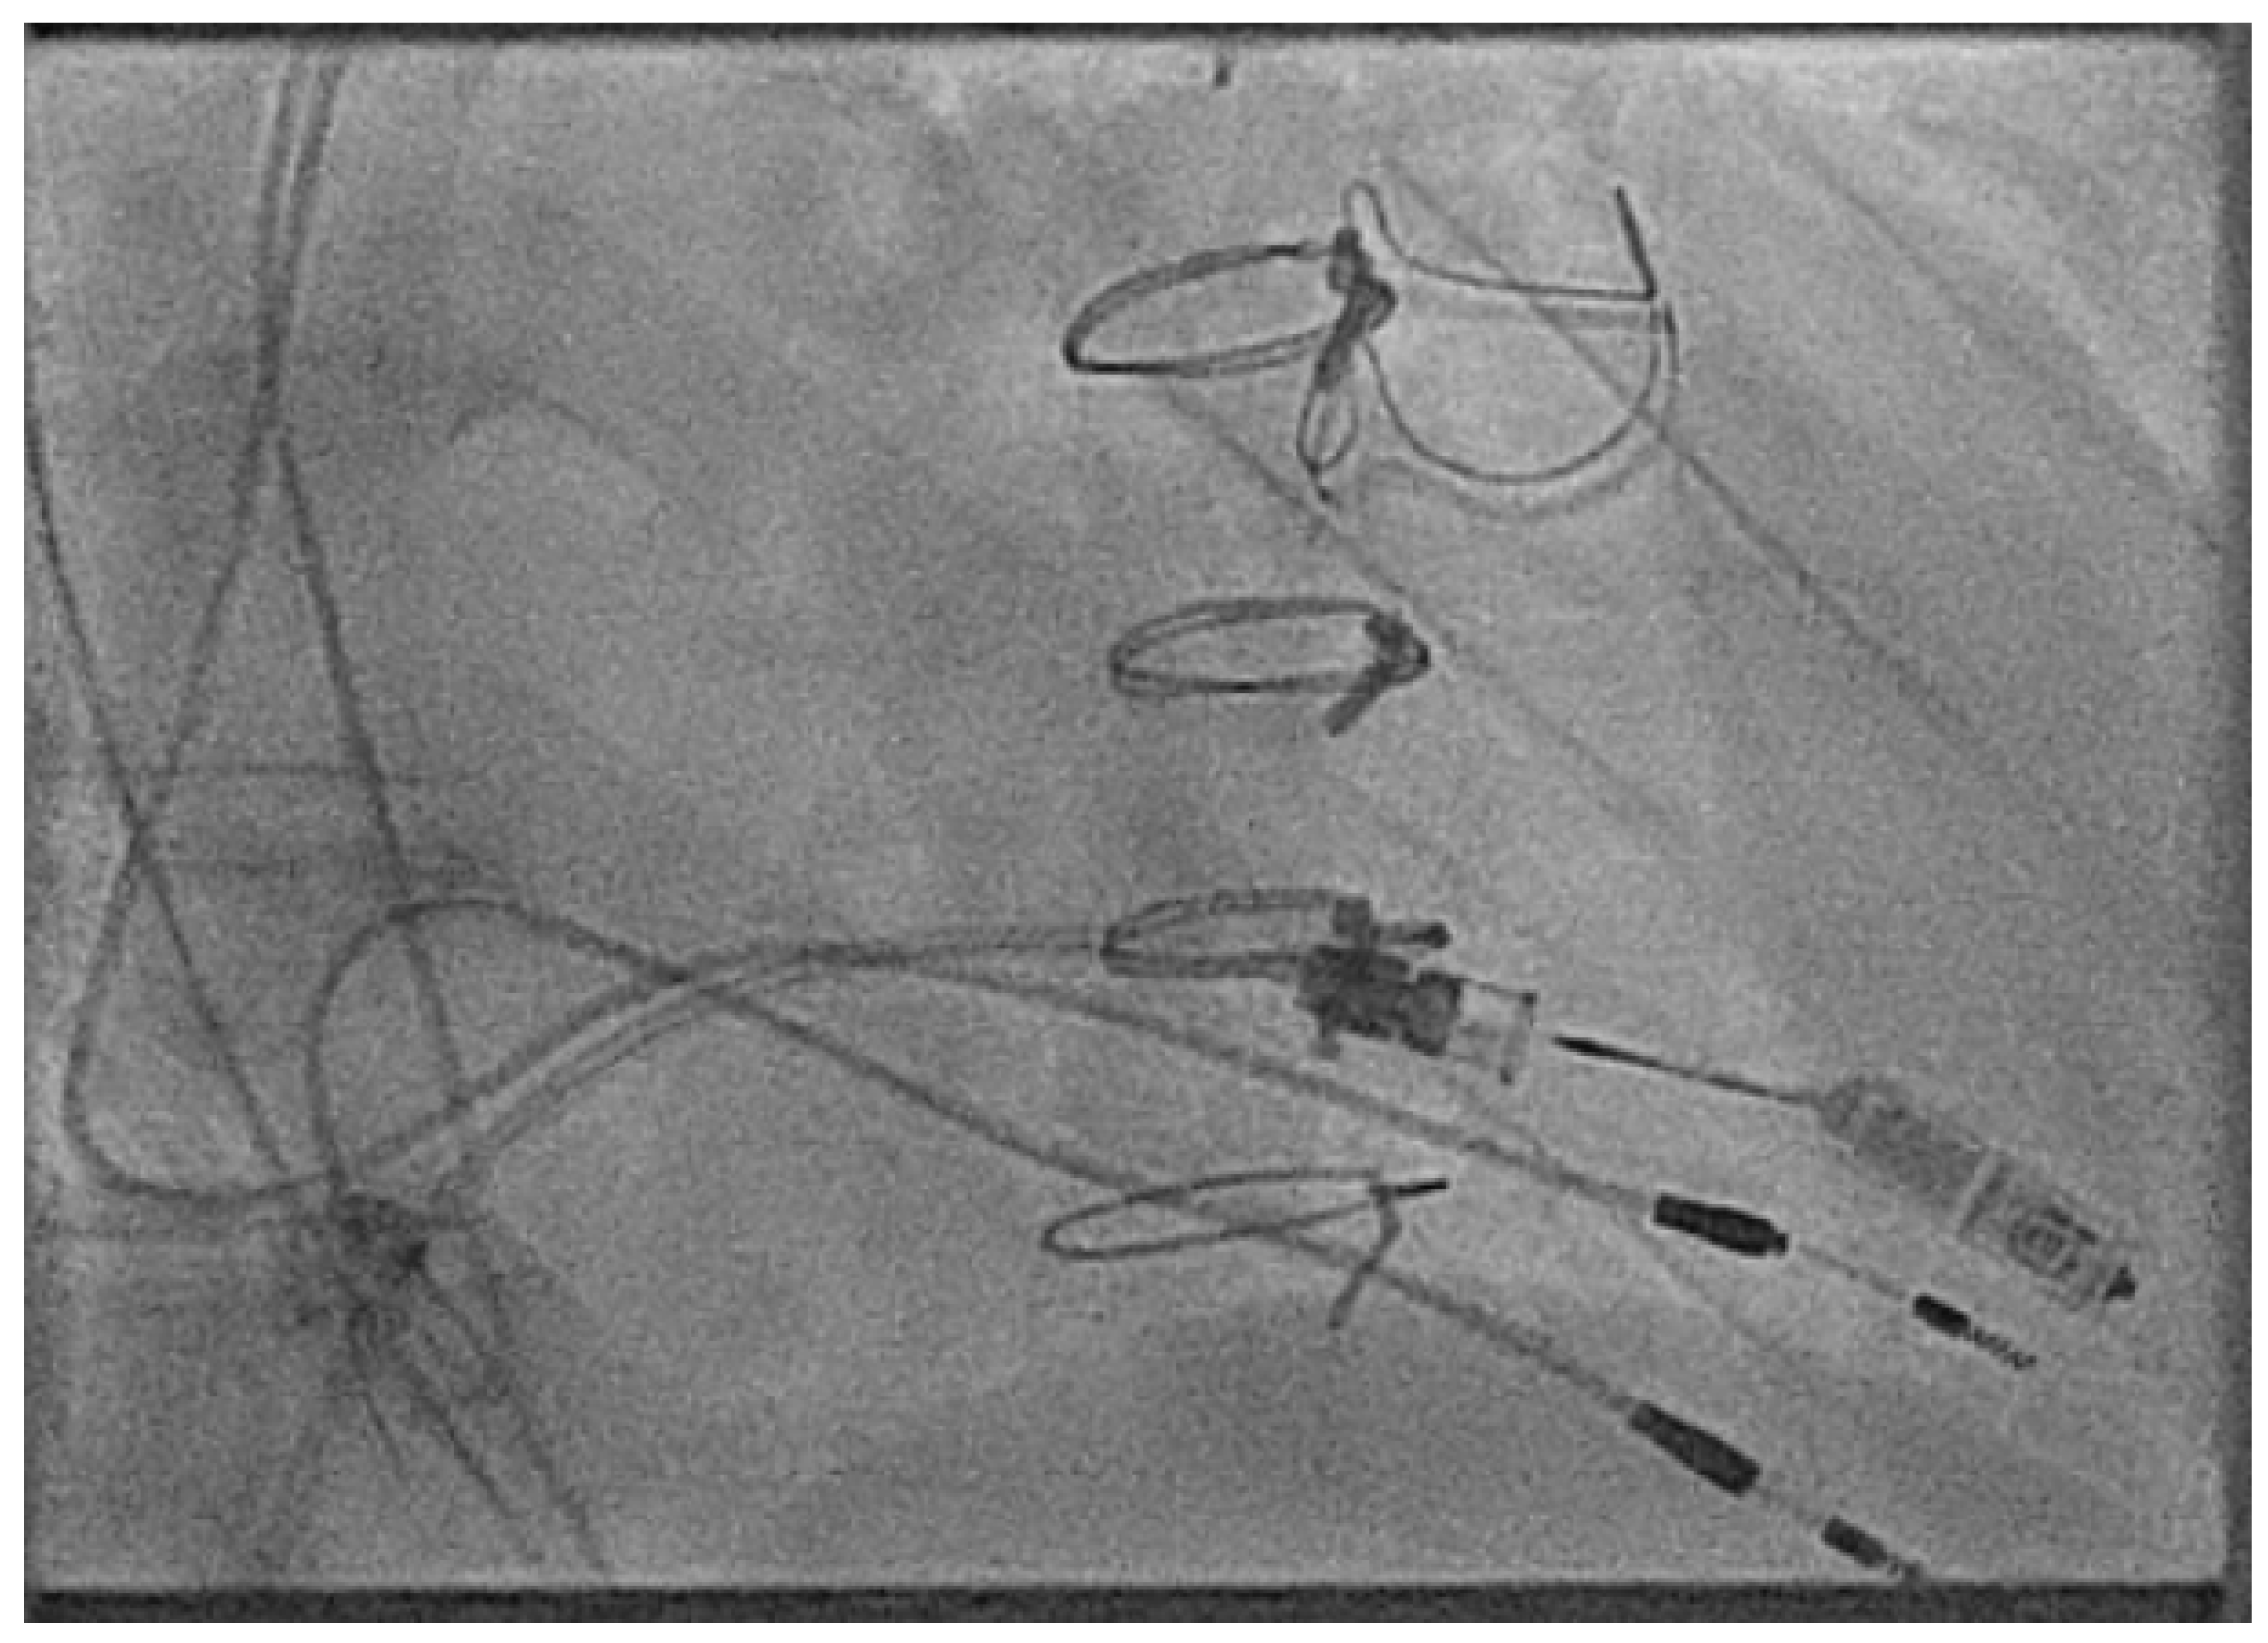

- Mitchell, A.J.; Murphy, N.; Walsh, K.P. Fist in man implantation of a leadless pacemaker in the left atrial appendage following Mustard repair. Europace 2021, 24, 795. [Google Scholar] [CrossRef]

- Hayle, P.; Altayeb, F.; Hale, A.; Rao, A.; Ashrafi, R. Case report demonstrating novel approaches for leadless pacemaker implantation in the single ventricle heart. Eur. Heart J. Case Rep. 2025, 9, ytaf146. [Google Scholar] [CrossRef]

- Goulden, C.J.; Khanra, D.; Llewellyn, J.; Rao, A.; Evans, A.; Ashrafi, R. Novel approaches for leadless pacemaker implantation in the extra-cardiac Fontan cohort: Options to avoid leaded systems or epicardial pacing. J. Cardiovasc. Electrophysiol. 2023, 34, 2386–2392. [Google Scholar] [CrossRef]